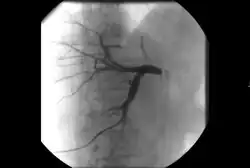

Takayasu arteritis angiography

Dissections can also arise in virtually any other artery. Carotid artery dissection, for example, places patients at increased risk for stroke and may extend further into the blood vessels within the brain. Vertebral artery dissection are less common but also dangerous for similar reasons. Mesenteric artery dissection may limit the blood supply to the intestines. Renal artery dissections can decrease blood flow to the kidneys and contribute to hypertension.[94] Peripheral arterial dissections can be found elsewhere in the arms and legs. These dissections can occur primarily due to focal traumas, underlying vascular disease, or as an extension of a larger, complex aortic dissection that tears further into these smaller branches.

Treatment of dissections depends on several factors, including the location, extent, how long it has been developing (acute or chronic) and whether it is limiting perfusion. Surgical approaches to dissections can include reconstructing the aorta, surgical bypass and surgical fenestration. Like other arterial disorders, endovascular approaches to dissection such as stent-grafting[95] and percutaneous fenestration[96] can be utilized, either primarily or in combination with surgery depending on the complexity of the dissection.